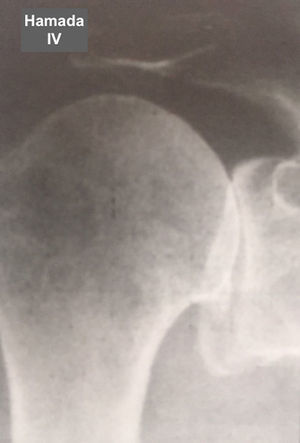

Fue elaborada por Hamada (tabla 6 y figs. 7–11) para describir el tipo de artropatía en roturas masivas del manguito de los rotadores. Utiliza la radiografía convencional y las características de la articulación glenohumeral y el ascenso de la cabeza del húmero para determinar el grado de la lesión. Muestra una correlación quirúrgica y radiológica de cerca del 80%10.